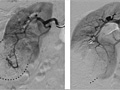

In some cases, a method called interventional radiology may be used during an angiogram to treat diseases. For example, a catheter can be used to open a blocked blood vessel, deliver medicine to a tumor, or stop intestinal bleeding caused by diverticular hemorrhage. To stop intestinal bleeding, the catheter is moved into the small artery where the bleeding is occurring, and medicine that narrows the artery or causes the blood to clot is injected through the catheter.

- Blood vessels that are not in their normal position may mean that a tumor or other growth is pushing against them.

- A narrow spot in an artery may mean that a fat deposit, calcium deposit, or clot is reducing blood flow through the blood vessel.

- A bulge in a blood vessel may mean a weakness in the blood vessel wall (aneurysm).

- Dye that leaks out of a blood vessel may mean a hole in the blood vessel.

- There is abnormal branching of blood vessels present since birth (congenital).

- An abnormal pattern of blood vessels may mean that a tumor is present.